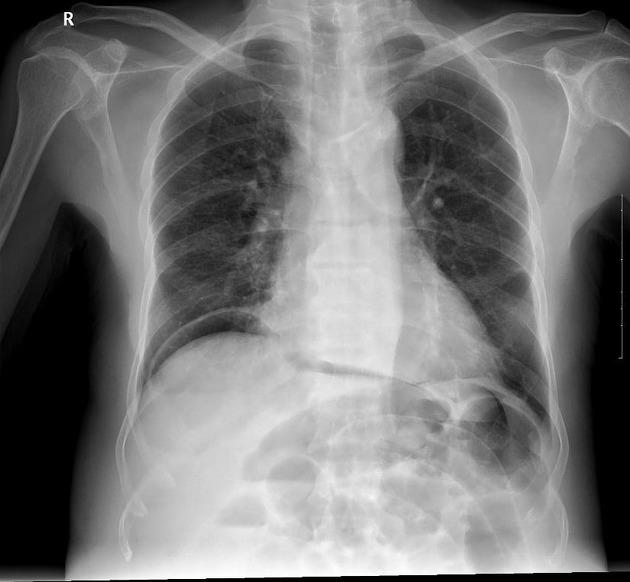

A 55-year-old woman arrives at an urgent care clinic complaining of acute, excruciating abdominal pain that began abruptly while she was working in her garden. She describes the pain as generalized and rapidly worsening over the last hour. She has a history of chronic low back pain for which she frequently uses over-the-counter naproxen, along with a history of gastroesophageal reflux disease, and smoking for 30 years. Upon examination, she is visibly distressed and her abdomen is diffusely rigid with marked tenderness to palpation and rebound. Bowel sounds are absent. Her temperature is 37.20C, blood pressure is 105/70 mmHg, pulse is 125/min, respirations are 24/min, and oxygen saturation is 96% on room air. Given this clinical presentation, what is the most appropriate diagnostic study and the immediate definitive management strategy?